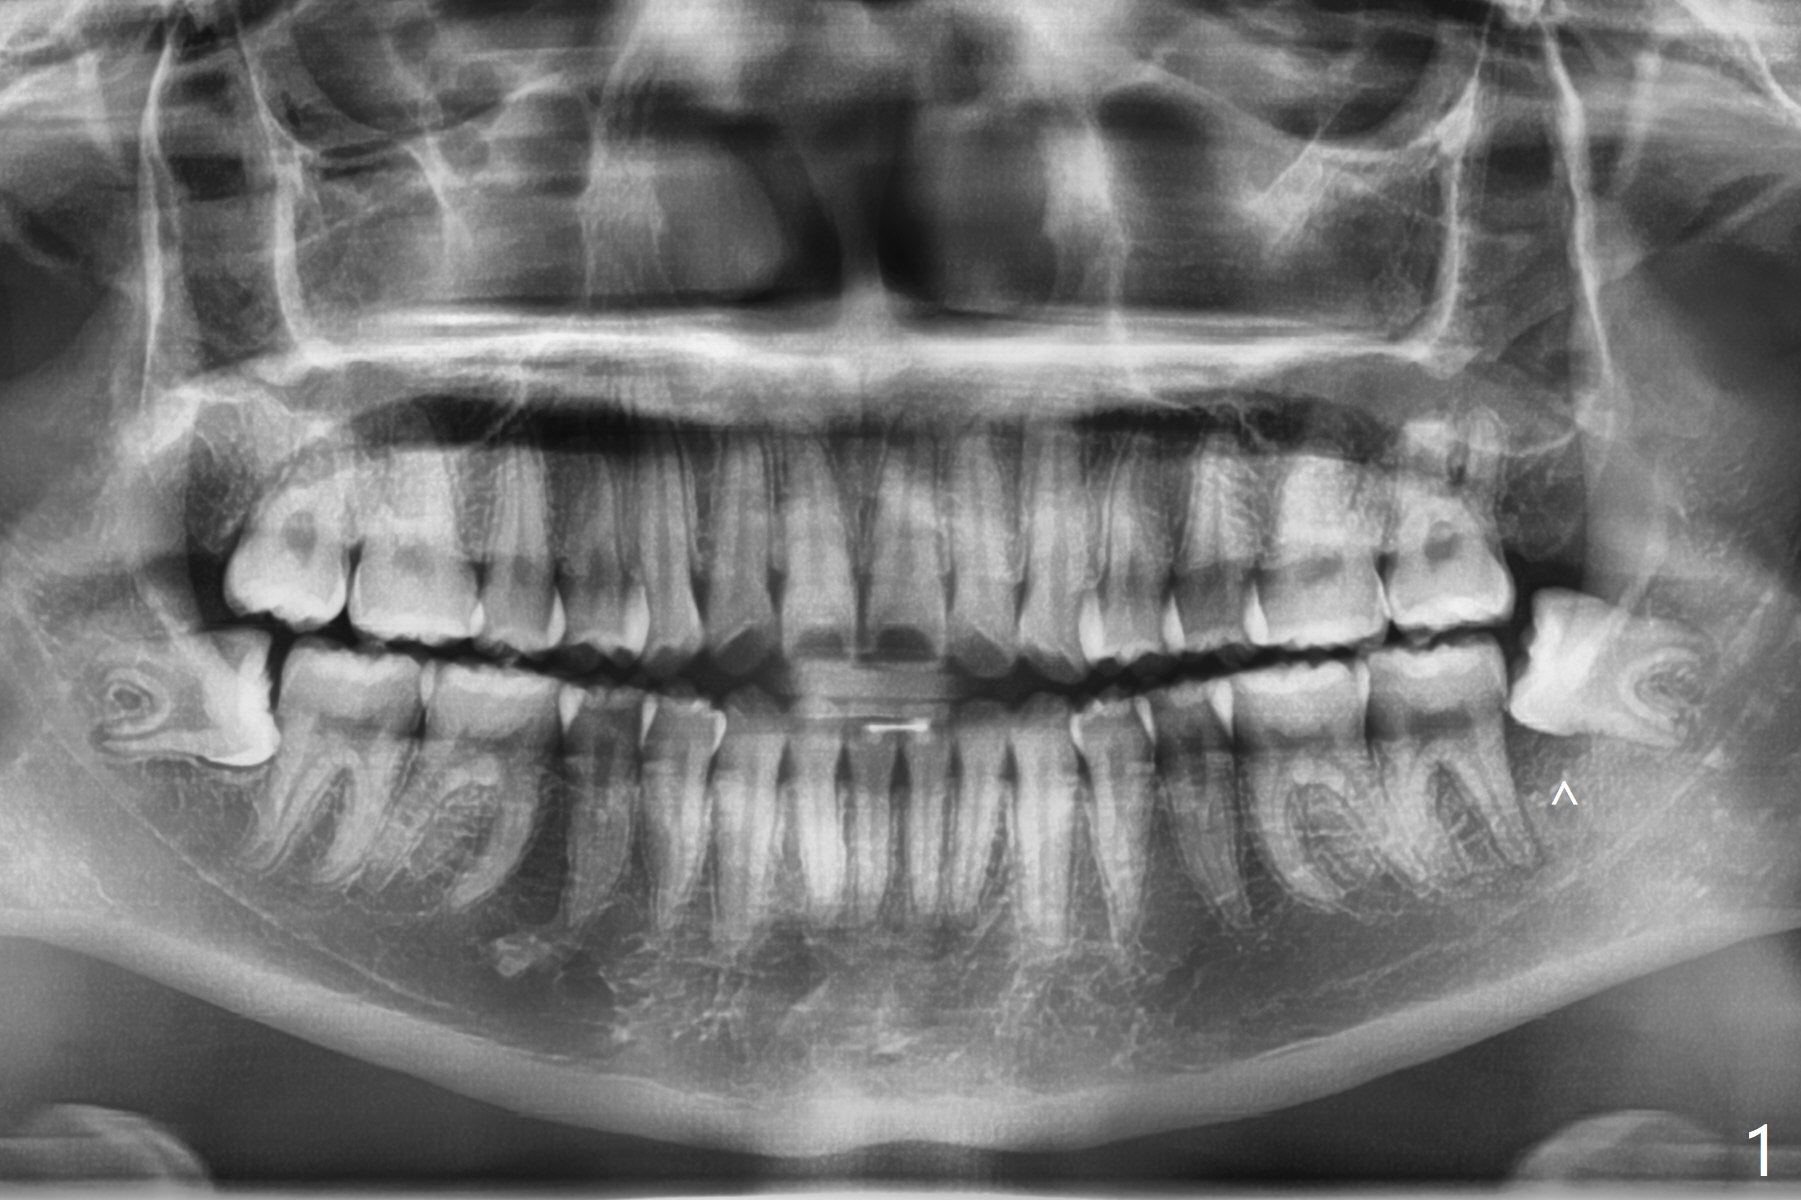

A 15.5-year-old woman with poor oral hygiene has pericoronitis at #17 extending to the left 2nd molar, corresponding to bone loss between them (Fig.1 ^). After extraction, a piece of Osteogen plug is placed horizontally as mesial as possible (Fig.2).